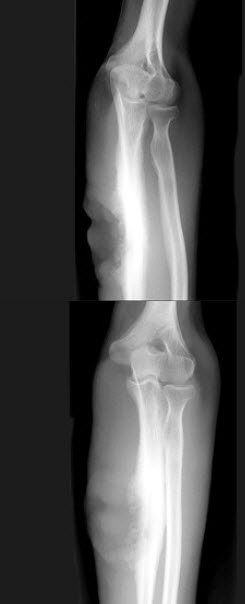

30、单项选择题

男孩,13岁,外伤后入院。结合图像,最可能的诊断是()

A.青枝骨折

B.右尺骨骨折

C.Colles骨折

D.Smith骨折

E.孟氏骨折